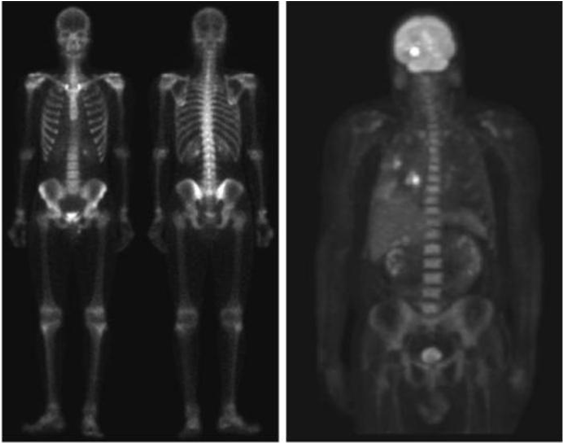

Gamma ray image

a) 환자에게 감마선을 방사하는 방사선 동위원소를 주사, 감마 검출기로써 영상을 획득 - 병소의 위치 파악에 유용

b) PET(positron emission tomography) image